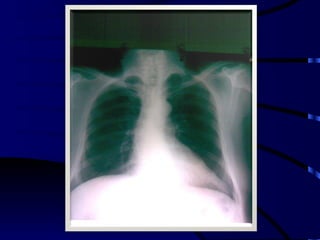

Derrame pleural izquierdo

Derrame pleural